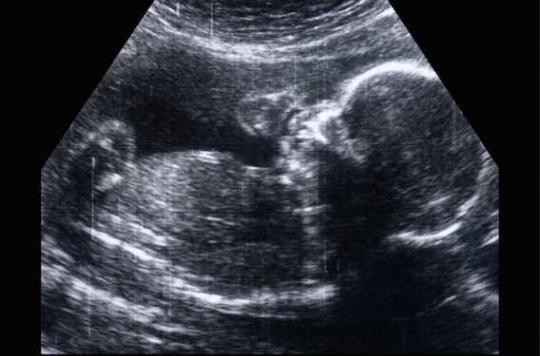

Il s’agit de déterminer si les effets tératogènes sur le fœtus, identifiés dans la littérature scientifique depuis les années 1980, ont été suffisamment relayés par ces acteurs, ou s’ils ont été sous-estimés, voire dissimulés. De même concernant les troubles moteurs, qui n’ont été intégrés au RCP (Résumé Caractéristique Produit) qu’en 2006, alors que les études les mentionnaient dès les années 1990.

De fait, de nombreux médecins semblent ne pas avoir été mis au courant des risques liés aux grossesses sous Dépakine. Selon nos informations, des fœtus ont ainsi été exposés à la molécule jusqu’en 2010.

Les praticiens sont-ils les seuls responsables, eux qui ont prescrit du Valproate de sodium sans informer les mères des risques élevés de malformation (spina bifida, notamment) et de troubles neurocomportementaux pour leur enfant ? Ou bien y a-t-il eu des manquements coupables de la part des fabricants et de l’Afsspas (devenue ANSM) ?